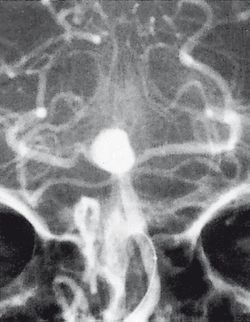

النزف تحت العنكبوتية فيه يحدث النزف ضمن الطبقة السحائية العنكبوتية. وأكثر الأسباب شيوعاً هو رضوض الدماغ، أما حالات النزف غير الرَّضِّيّ فتنتج عادة من انفجار أم دم aneurysm (وهي توسع كيسي غير طبيعي في شريان أو أكثر). ومن الأسباب الأخرى التشوهات الشريانية الوريدية، والتهاب الأوعية، وتسلخ الشرايين، واعتلالات التخثر، وخثار الجيوب الوريدية، وفقر الدم المنجلي، وتمزق شريان سطحي صغير. ويبقى السبب مجهولاً في نحو 14ـ22% من الحالات. وفيما يأتي نبذة عن النزف تحت العنكبوتية الناتج من أمهات الدم لكونه الأهم بينها.

يعتمد بصفة رئيسة على تصوير الدماغ، ومن أكثر طرق التصوير استعمالاً التصوير الطبقي المحوري (الشكل 3)، وبدرجة أقل المرنان المغنطيسي. وجدير بالذكر أن تصوير الدماغ قد يخفق في إظهار النزف في نحو 5% من المرضى، وفي هذه الحالة يمكن اللجوء إلى استقصاء آخر هو البزل القطني للسائل الدماغي الشوكي. وتظهر دراسة السائل وجود أعداد كبيرة من الكريات الحمر، مما يثبت حدوث النزف.